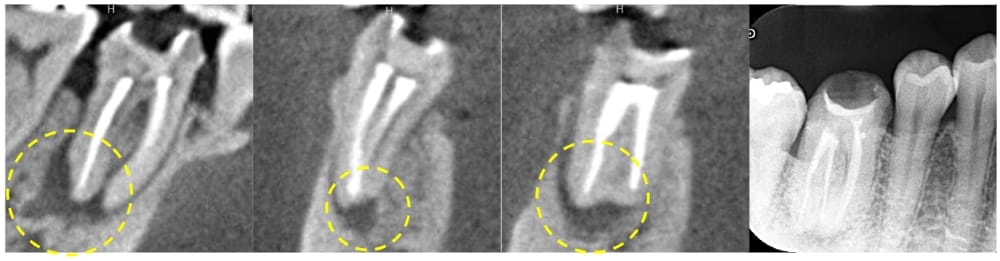

6ヶ月後の経過観察時には初診時の噛んだ時の鈍痛は消失していました。レントゲン、CTにて、根尖部の明瞭な骨の回復が認められ、治療がうまく奏功していることが確認できました。

通常であれば術後12ヶ月まで経過をみますが、骨も完全に回復していること、症状がないことから、かかりつけ歯科医院にて最終補綴(かぶせもの)を行ってもらうことになりました。